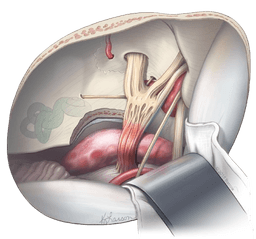

Microvascular Decompression-MVD

Microvascular decompression (MVD) is a surgical intervention performed to relieve abnormal compression of a cranial nerve causing trigeminal neuralgia, glossopharyngeal neuralgia, or hemifacial spasm. Specifically, MVD in India is a surgery that is performed to relieve symptoms of pain and muscle twitching caused due to nerve compression by an artery or vein. To achieve this, the surgery procedure involves the direct access of the skull by opening and exposing the nerve at the base of the brainstem to insert a small sponge between the compressing vessel and the nerve. In this process, the small incision or cut is made behind the ear. Then, while viewing the trigeminal nerve through a microscope, the surgeon places a soft cushion between the nerve and injured blood vessels. Ultimately, the main goal of MVD is to identify and relieve pressure from one or more blood vessels. This step is crucial in finding blood vessels pressing on the trigeminal nerve and gently shifting them away. Finally, a small cushion is placed between them to prevent the pressure and relieve pain.